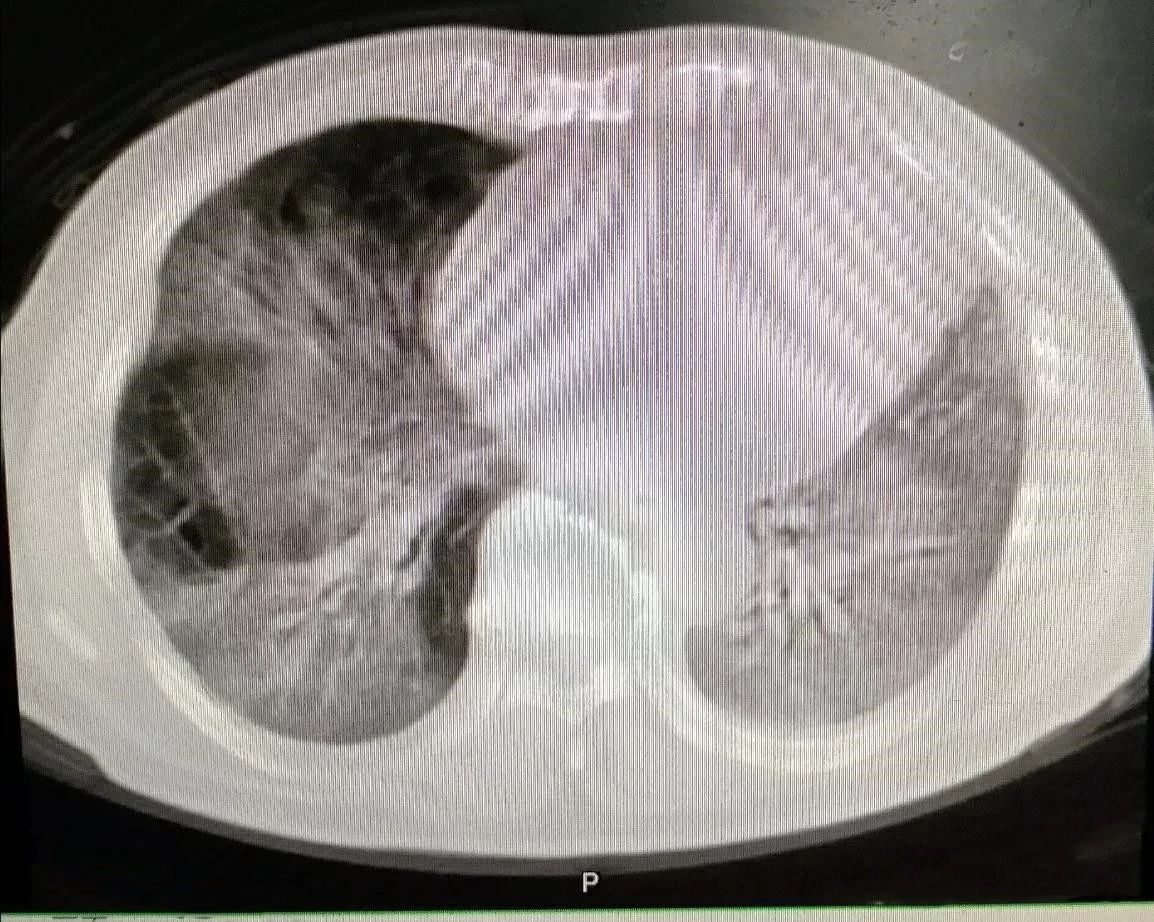

下图是同一位患者三次CT检查的图像,每次检查相隔2天,我们来看看肺部的变化。

大家可以很清楚地看到,右侧(患者的左胸)肺部全变白了,左侧(患者右胸)变白的面积也是非常大。

正常的肺组织里含有大量的空气,对X线的阻挡能力很弱,所以在X线下呈现黑色。当肺部出现炎症反应,大量蛋白、组织液、白细胞等渗出,肺间质充血、水肿等,这时的肺组织对X线的吸收能力就明显增强了,有点像实质器官的表现,所以呈现出白色。

变成白色的肺组织,基本上失去了气体交换的能力,患者会感到明显的缺氧,呼吸困难。我们需要给患者吸氧,重症者上呼吸机,甚至动用ECMO进行治疗。上面我举例的这位患者,就是一位新型冠状病毒感染的患者,最终由于病情发展太快,而不幸死亡。